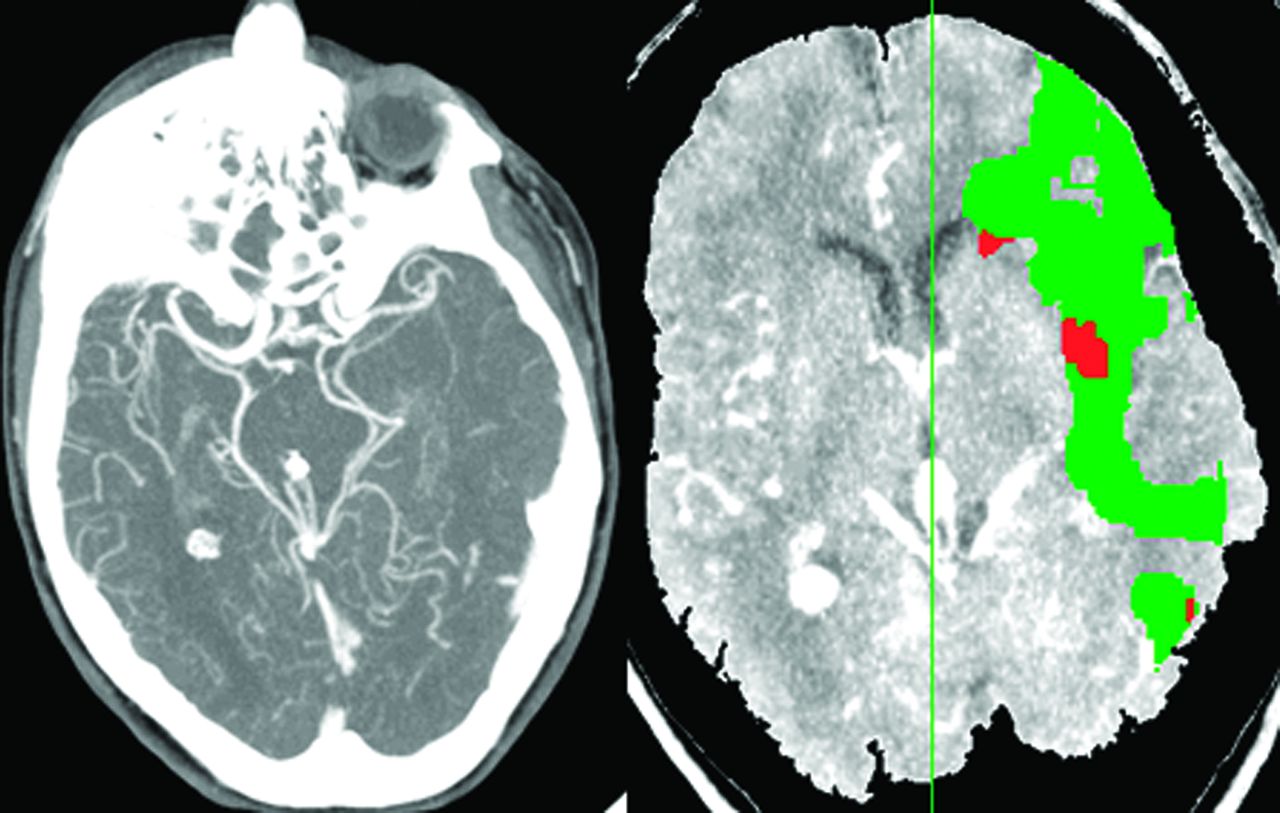

灌注CT是第二个成像模式被用来确定一个近似的半影急性缺血性中风患者。灌注CT图像上获得超快的CT扫描仪通过快速重复扫描后注入碘化对比材料。与一个信号冲刷bolus-contrast灌注CT扫描生成的曲线,可以生成cb v半定量的cb v和地图都未都未。26cb v随着缺血变得更严重,崩溃,都未与灌注CT缺血性核心被确定为一个地区与cb v明显下降。都未CBF和MTT地图展示缺血灌注值低于一个阈值定义为异常的地区的大脑区域。缺血半影操作上定义为该地区的CBF cb v或MTT异常值高于都未崩溃的阈值(图2)。27,28使用灌注CT是目前受到几个因素,与DWI-PWI相比。这些因素是有限的报道缺血性脑(只有2 - 4片对于大多数扫描仪,尽管整个大脑覆盖率现在可以在更新模型),更可靠地确定阈值识别CBF cb v / MTT和异常,都未和小动物成像技术建模工作。灌注CT的一个主要优点是更广泛的可用性和访问与MRI相比。样本大小适度的做的一项研究证明类似目标的识别病人的治疗决定3 -见到时间窗与灌注CT与DWI-PWI相比,但这一发现需要确认更多的患者在多个网站。29日当一些与灌注CT解决当前的问题和可比性DWI-PWI界限不明的近似被证实,实际问题表明,它将成为最常用的成像工具界限不明的近似。